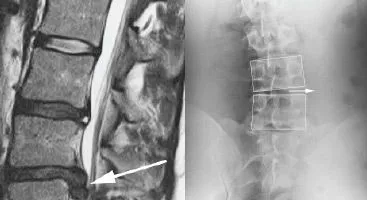

MD with a Lumbar Disc Herniation

Andrew was a medical doctor who was diagnosed with a herniated disc between L4 and L5. It caused local back pain that radiated down his right leg into his calf, which made it difficult for him to stand for long periods of time while he saw patients.